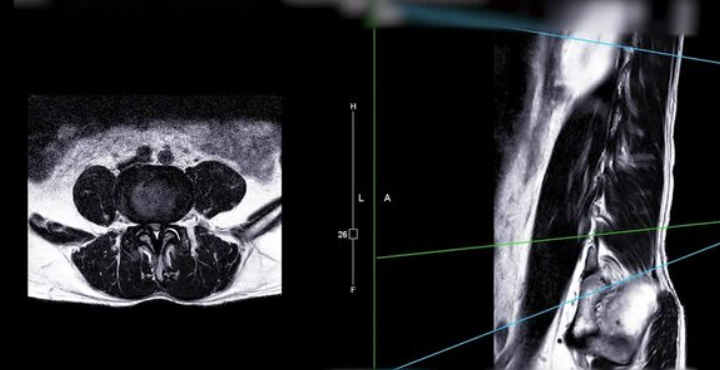

허리디스크, 또는 요추 추간판 탈출증은 척추 뼈 사이의 디스크가 손상되어 신경을 압박하는 질환입니다. 이 상태는 통증, 마비, 감각 이상 등 다양한 증상을 유발할 수 있으며, 일상 생활에 큰 지장을 줄 수 있습니다. 허리디스크의 증상은 개인마다 다르게 나타나지만, 일반적으로 몇 가지 공통적인 증상들이 있습니다.

허리디스크는 또한 신경 압박을 유발하여 바늘로 쏘이는 듯한 통증, 찌릿한 통증 또는 영향을 받는 신경 경로를 따라 감각 상실과 같은 증상을 나타낼 수 있습니다. 좌골 신경통은 허리에서 엉덩이를 거쳐 한쪽 다리 뒤쪽으로 퍼지는 통증이 특징이며, 다리나 발의 저림, 따끔거림 또는 근력 약화가 동반될 수 있습니다.

허리디스크로 인한 다리저림은 흔히 겪을 수 있는 증상 중 하나입니다. 이는 척추의 디스크가 탈출하거나 돌출되어 신경을 압박함으로써 발생합니다. 특히, 척추의 하부인 요추 부위에 문제가 생겼을 때 다리에 저림이나 통증을 느낄 수 있습니다. 이러한 증상은 장시간 앉아 있거나 서 있을 때 더욱 심해질 수 있으며, 때로는 걷거나 서 있는 것조차 어렵게 만들 수 있습니다.

중요한 것은 적절한 진단을 받는 것입니다. 의사는 환자의 증상을 평가하고 MRI나 CT 스캔과 같은 영상 진단을 통해 허리디스크의 정도를 확인할 수 있습니다. 이를 통해 가장 적합한 치료 방법을 결정할 수 있습니다.